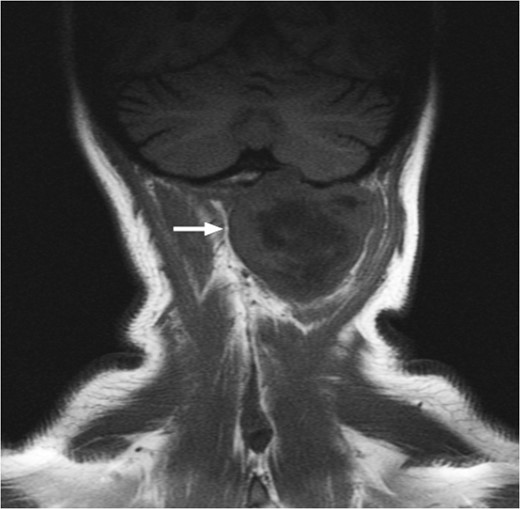

T1-weighted MRI showing the lesion in the posterosuperior aspect of the left neck arising at the level of C1, eroding through the C1 vertebra and displacing the thecal sac.